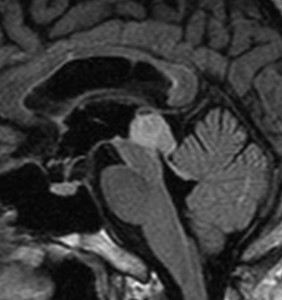

17歳で滑車神経麻痺で発症した例

中脳左下丘から上髄帆が腫大しています。滑車神経の出口にあたる部分が侵されていて症状と一致する所見です。右側のガドリニウム増強T1でも増強される部分はありません。確かにtectal gliomaの性質を有していて,3年間ほとんど動きませんでした。piaを押して突出するような腫瘤形成があり,diffuse astrocytomaともまた違う画像所見と言えます。滲み込む infiltrateというより,塊 solid massを作るという形質があるのがtectal gliomaでしょう。